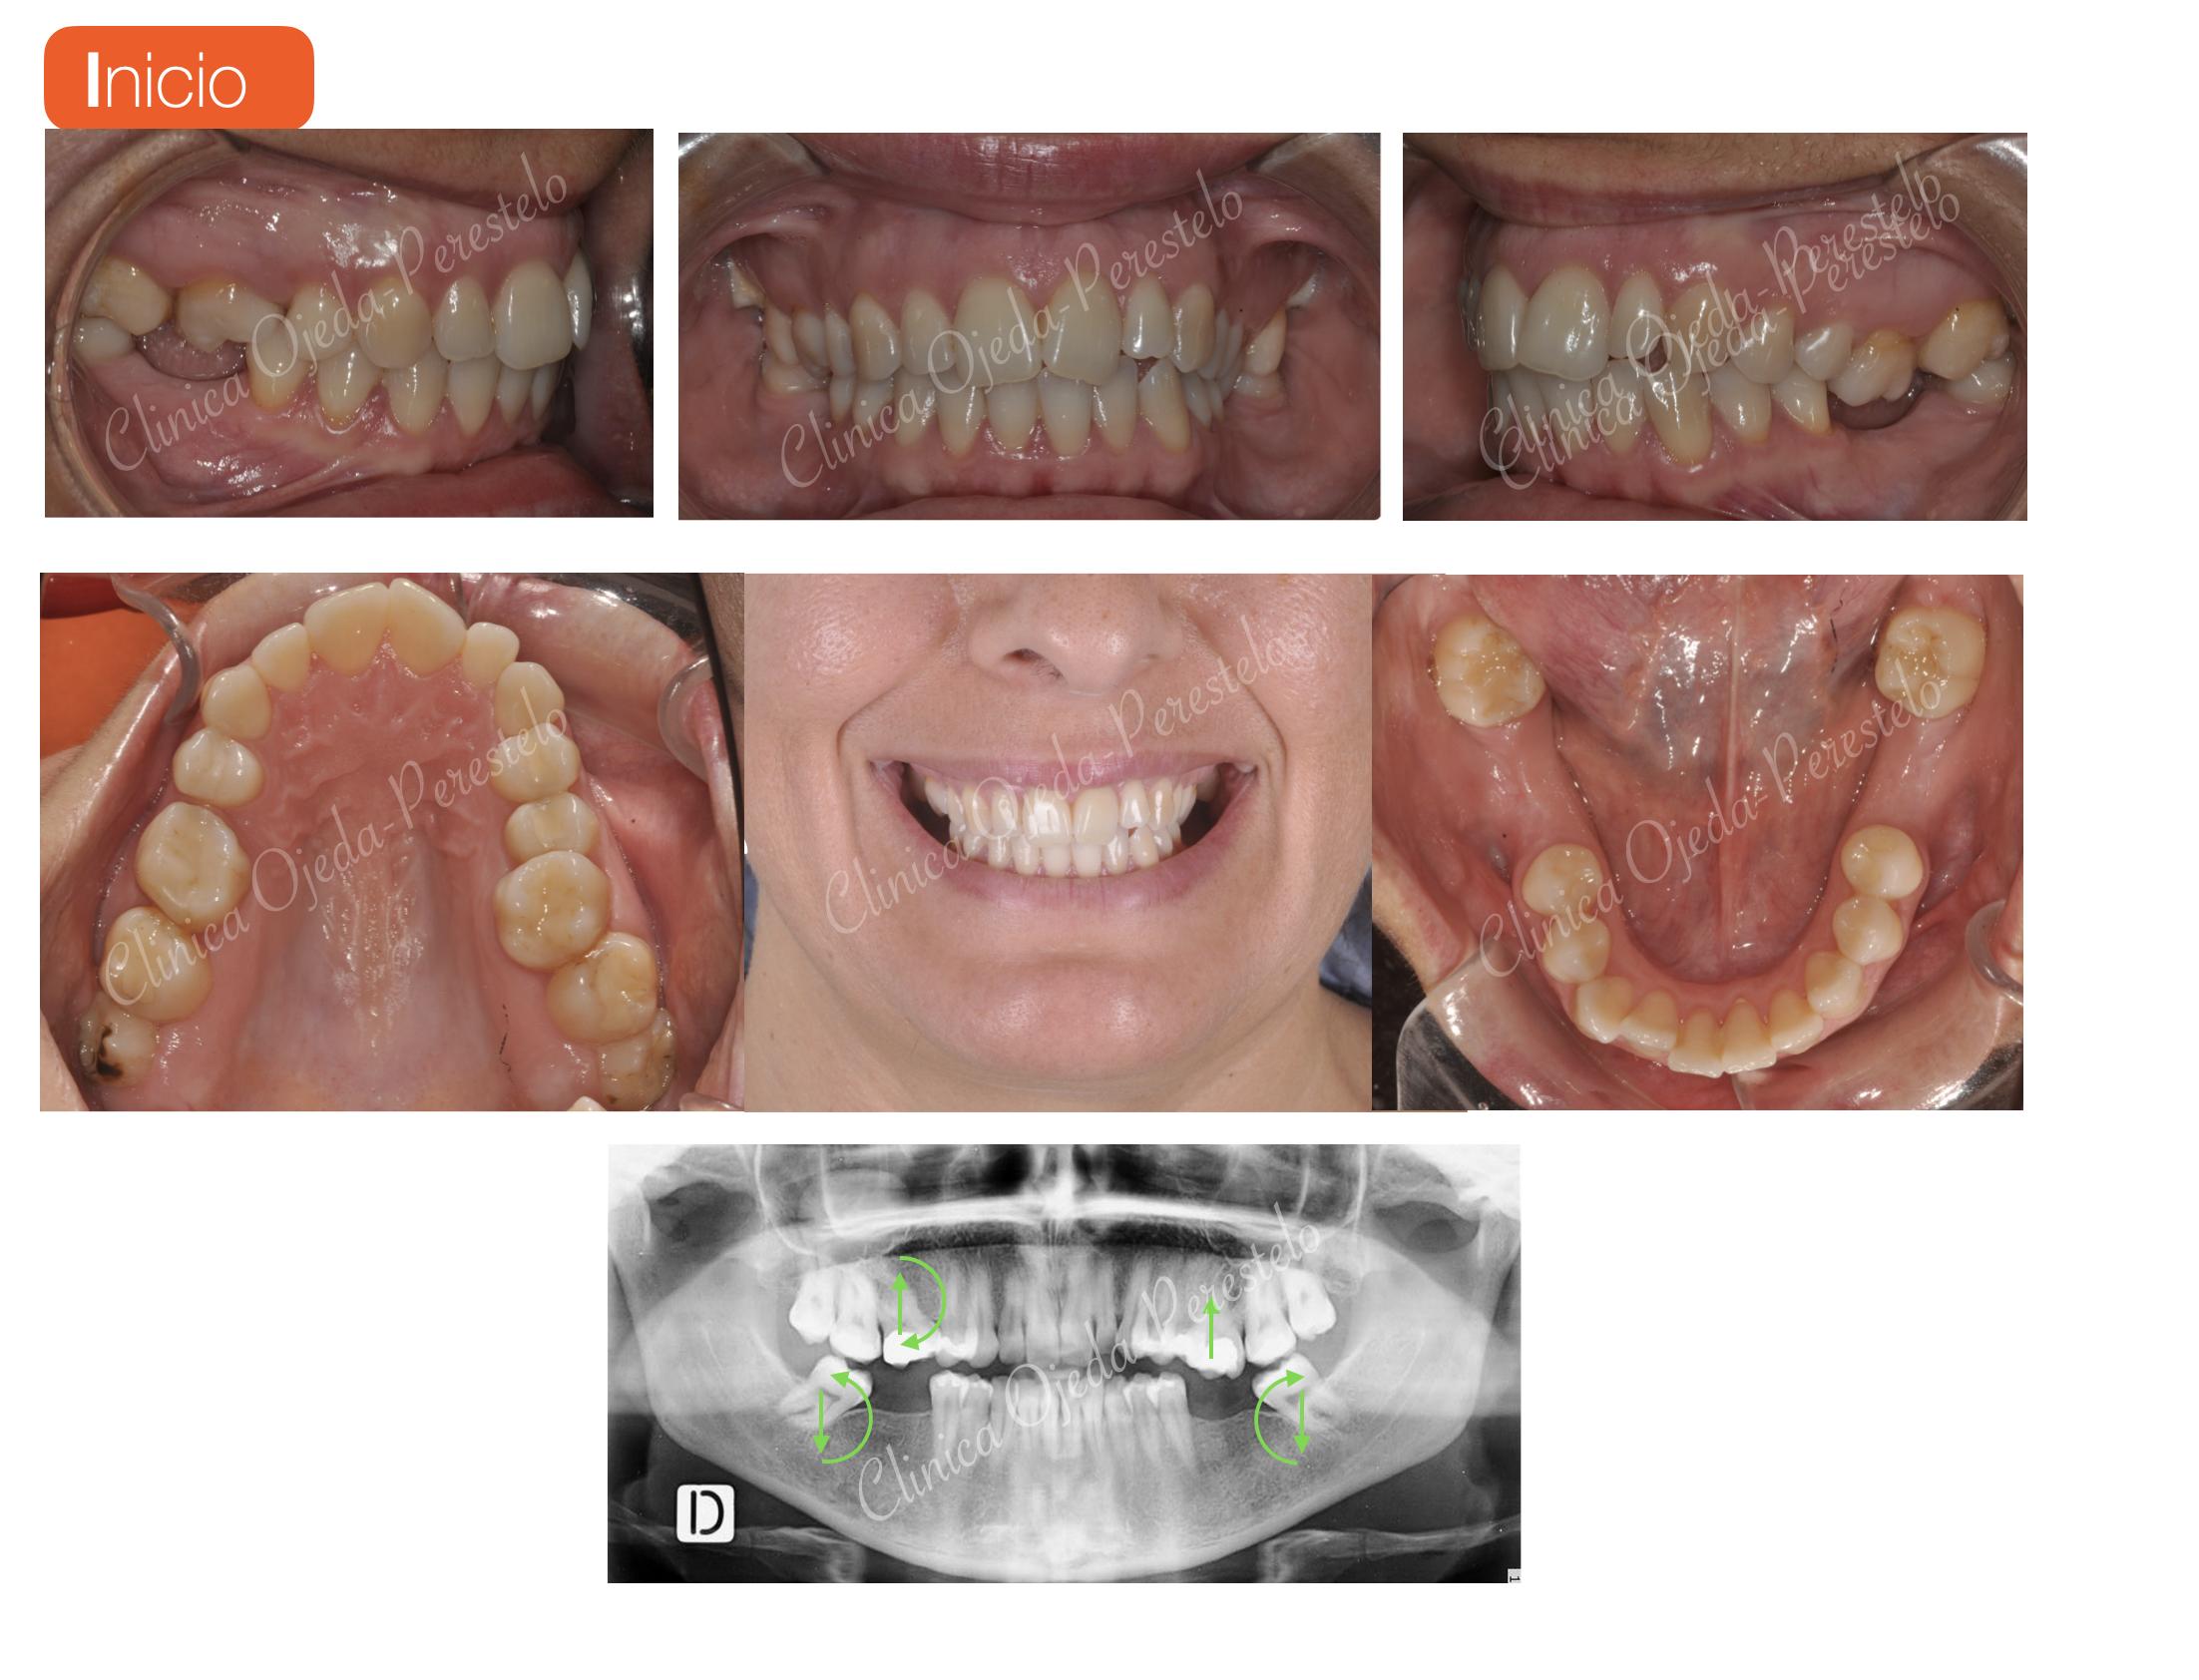

Decidimos comenzar tras la fase de Higienización Bucal  con el tratamiento de ortodoncia Prealineadores. La idea que hay detrás de esta miniortodoncia preliminar es disminuir el número de alienadores totales en torno a un 25%. Esta estrategia la denominamos hibridación y esta destinada a enderezar e intruir de los molares. (Dr Ojeda-Perestelo)

A continuación realizamos la alineación y nivelación de las arcadas dentarias (Dr Ojeda-Perestelo) y adecuamos los espacios para la colocación de implantes en posición 46,36,37 (Dr Acorán Borges). Además se decidió dotarle a la pieza 22 (microdóntica) de una proporción similar a la pieza 12 con un microrelleno de la misma (Dra Trinidad Gandía)